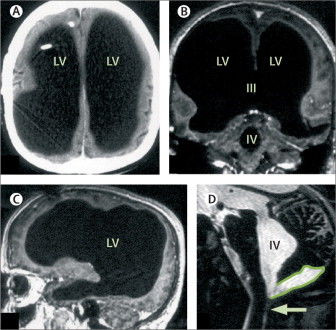

Bệnh nhân người Pháp phải nhập viện sau khi cảm thấy chân trái của mình yếu đi trong hai tuần. Trong quá trình chẩn đoán bệnh, ông được thực hiện nhiều xét nghiệm. Các bác sĩ đã vô cùng ngạc nhiên khi ảnh chụp não của não của bệnh nhân lại không phải não mà là một khoang chứa đầy chất lỏng khổng lồ.

Ảnh chụp não toàn chất lỏng của bệnh nhân.

Thế nhưng kết quả quét não đã khiến tất cả phải giật mình. Não bộ của ông đã sưng lên quá nhiều, chứa đầy dịch tủy, và thứ dịch ấy gần như đã thay thế toàn bộ khối óc, chỉ để lại một lớp vỏ não mỏng chứa các neuron thần kinh. Nói cách khác, người đàn ông này gần như không có não.

Việc chất lỏng lưu thông khắp não là bình thường. Tuy nhiên ở trường hợp này, thay vì được đưa vào hệ thống tuần hoàn, chất lỏng trong não người đàn ông này tích tụ lại. Cuối cùng, sự tích tụ chất lỏng chiếm hết không gian trong sọ, chỉ có một lượng siêu nhỏ là não thực sự.